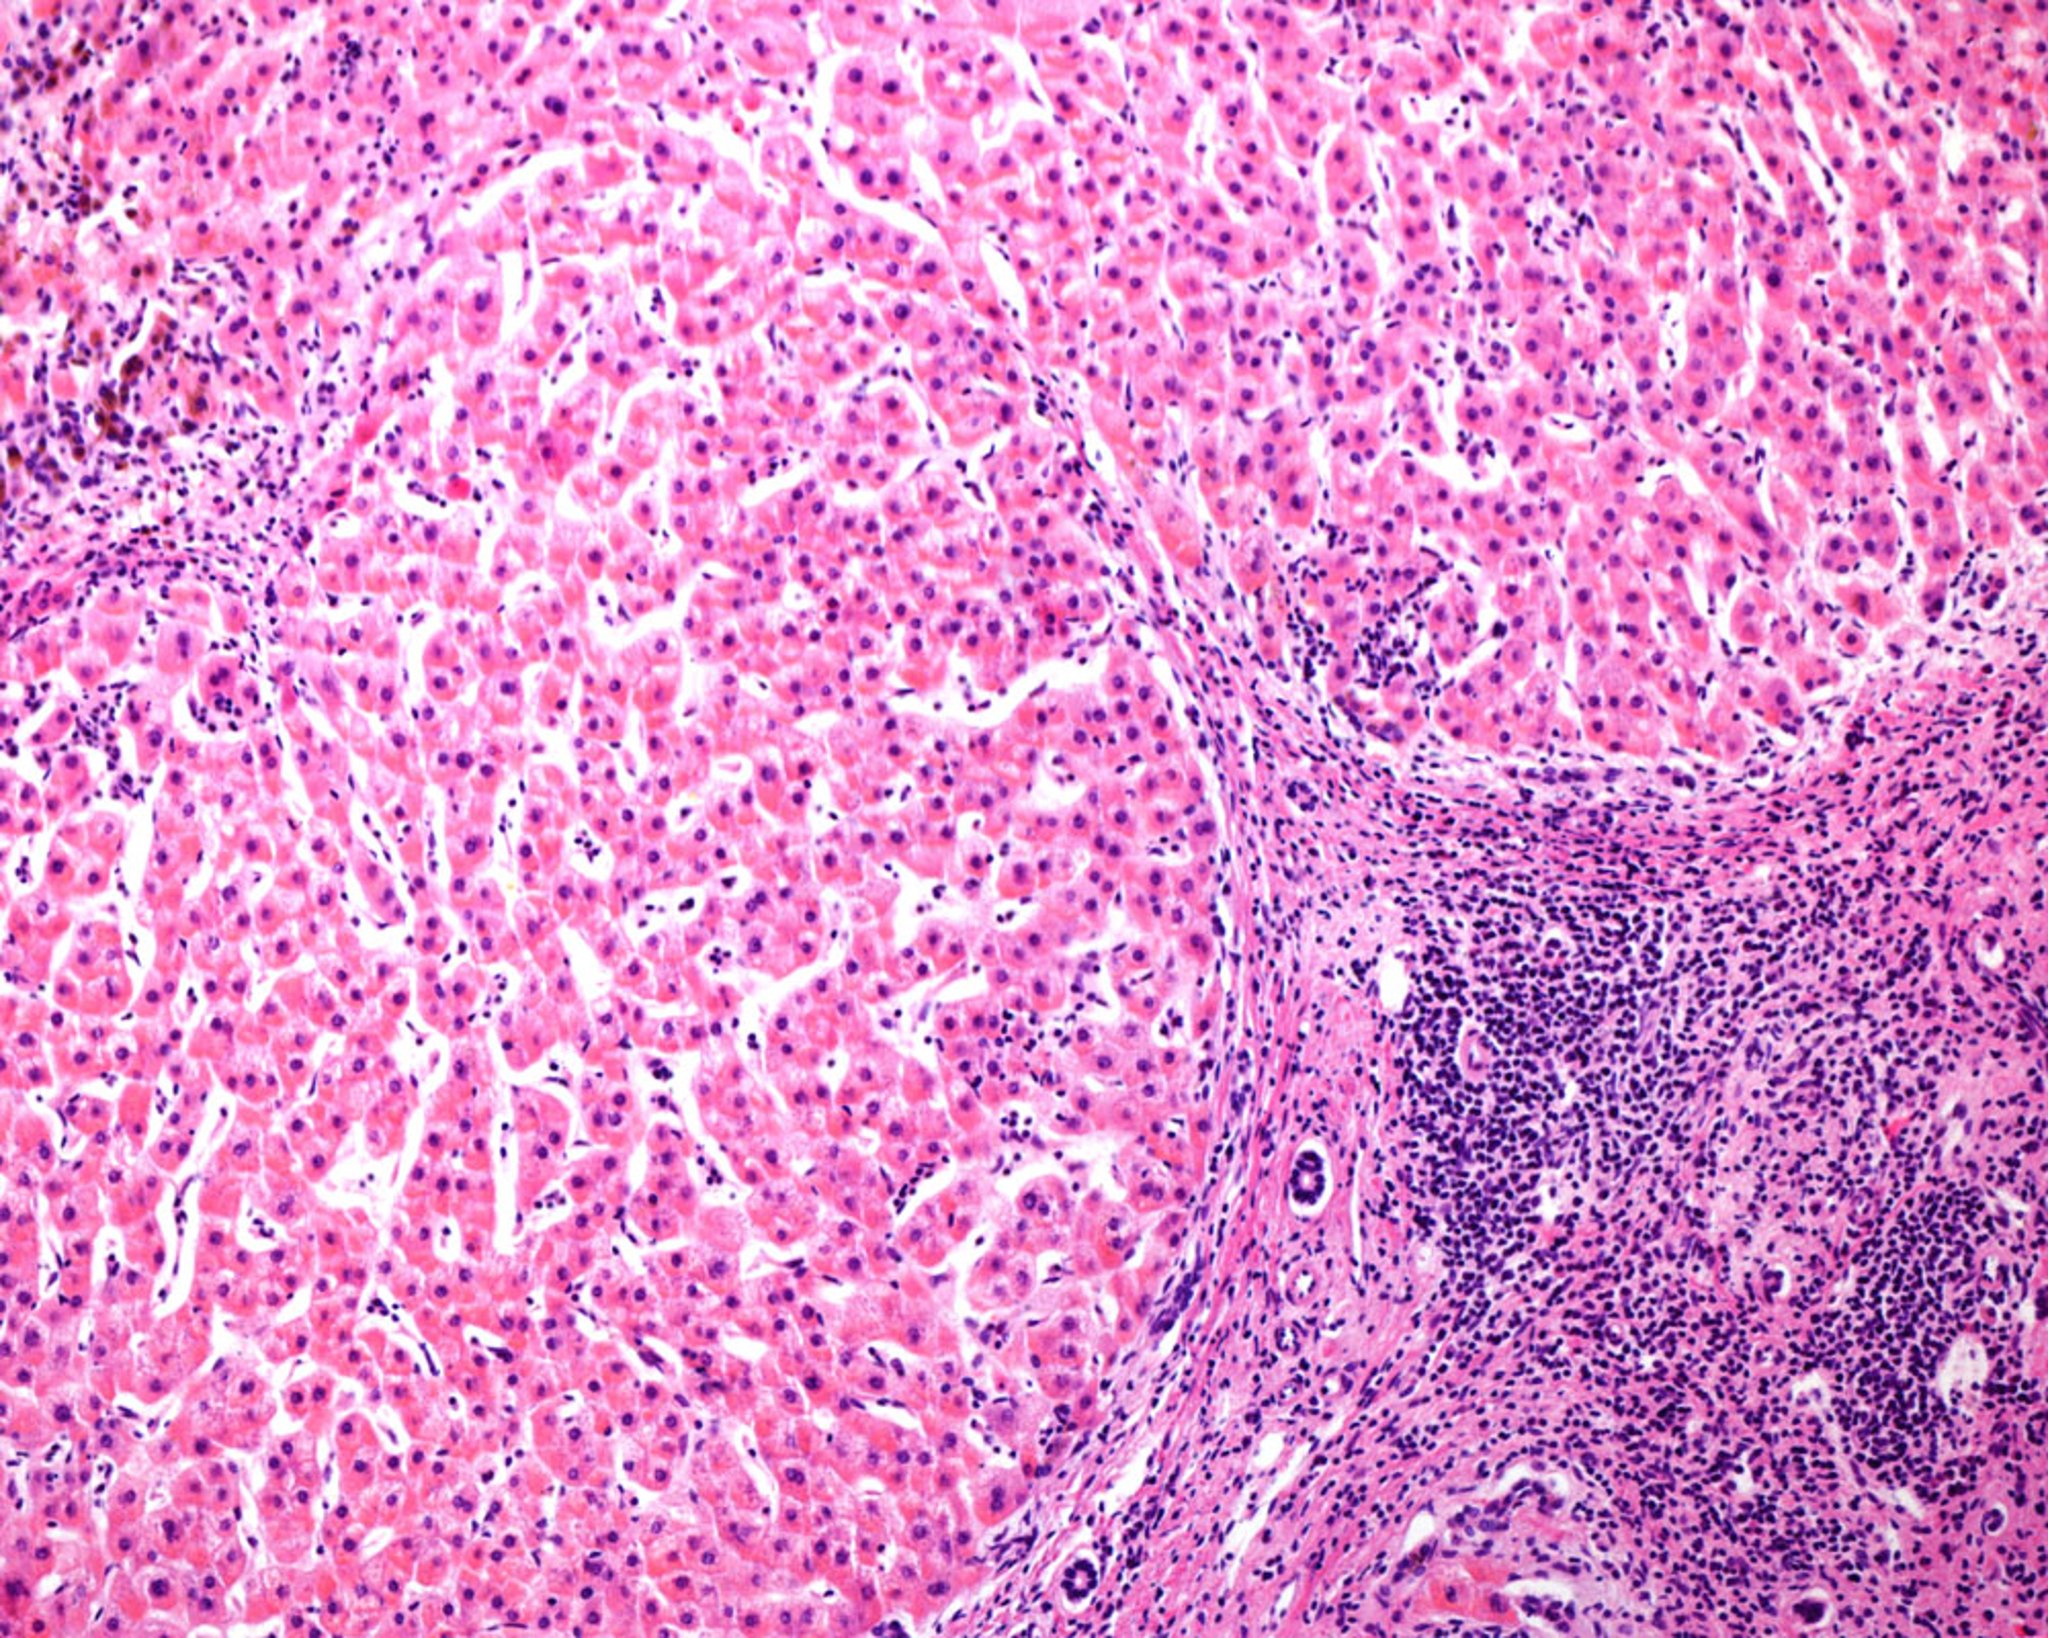

Cirrose micronodular no fígado humano (microscopia óptica)

Micrografia óptica de um fígado humano com cirrose micronodular, uma consequência frequente da hepatite alcoólica. Os nódulos regenerativos são separados por septos de tecido conjuntivo que mostram infiltrados inflamatórios crônicos. Observe a ausência de uma veia central nos nódulos e de tríades portais nos septos de tecido conjuntivo.

JOSE CALVO / SCIENCE PHOTO LIBRARY